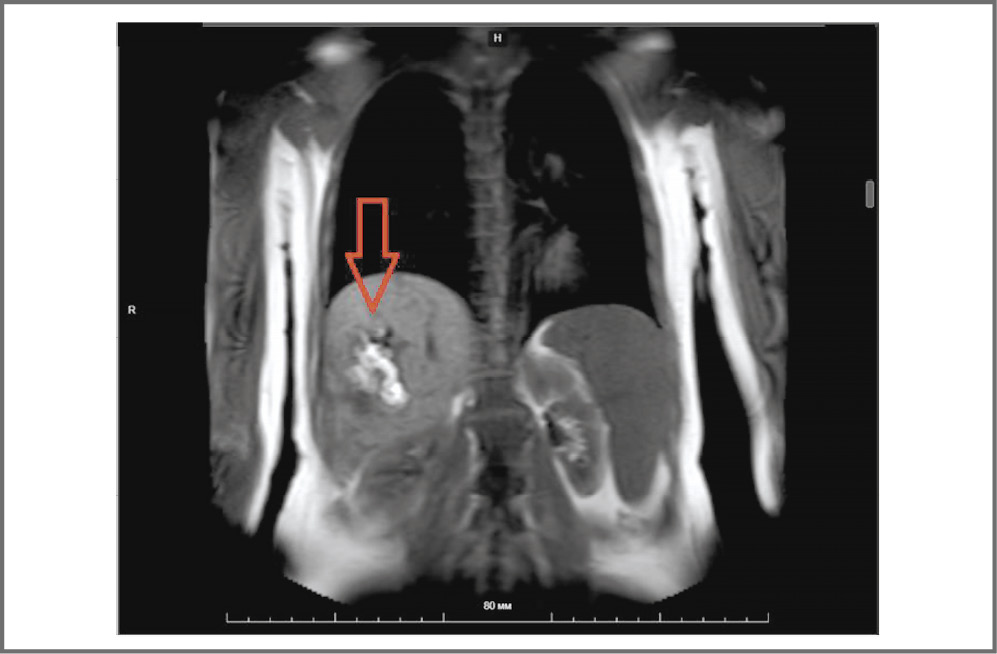

По данным магнитно-резонансной томографии органов брюшной полости с внутривенным контрастным усилением выявлены АВМ в VI, VII сегментах правой доли печени размерами до 27,5×23,5 мм и до 36,5×19 мм (рис. 3).

Рис. 3. АВМ печени у пациентки З. (магнитно-резонансная томография): фронтальная плоскость.